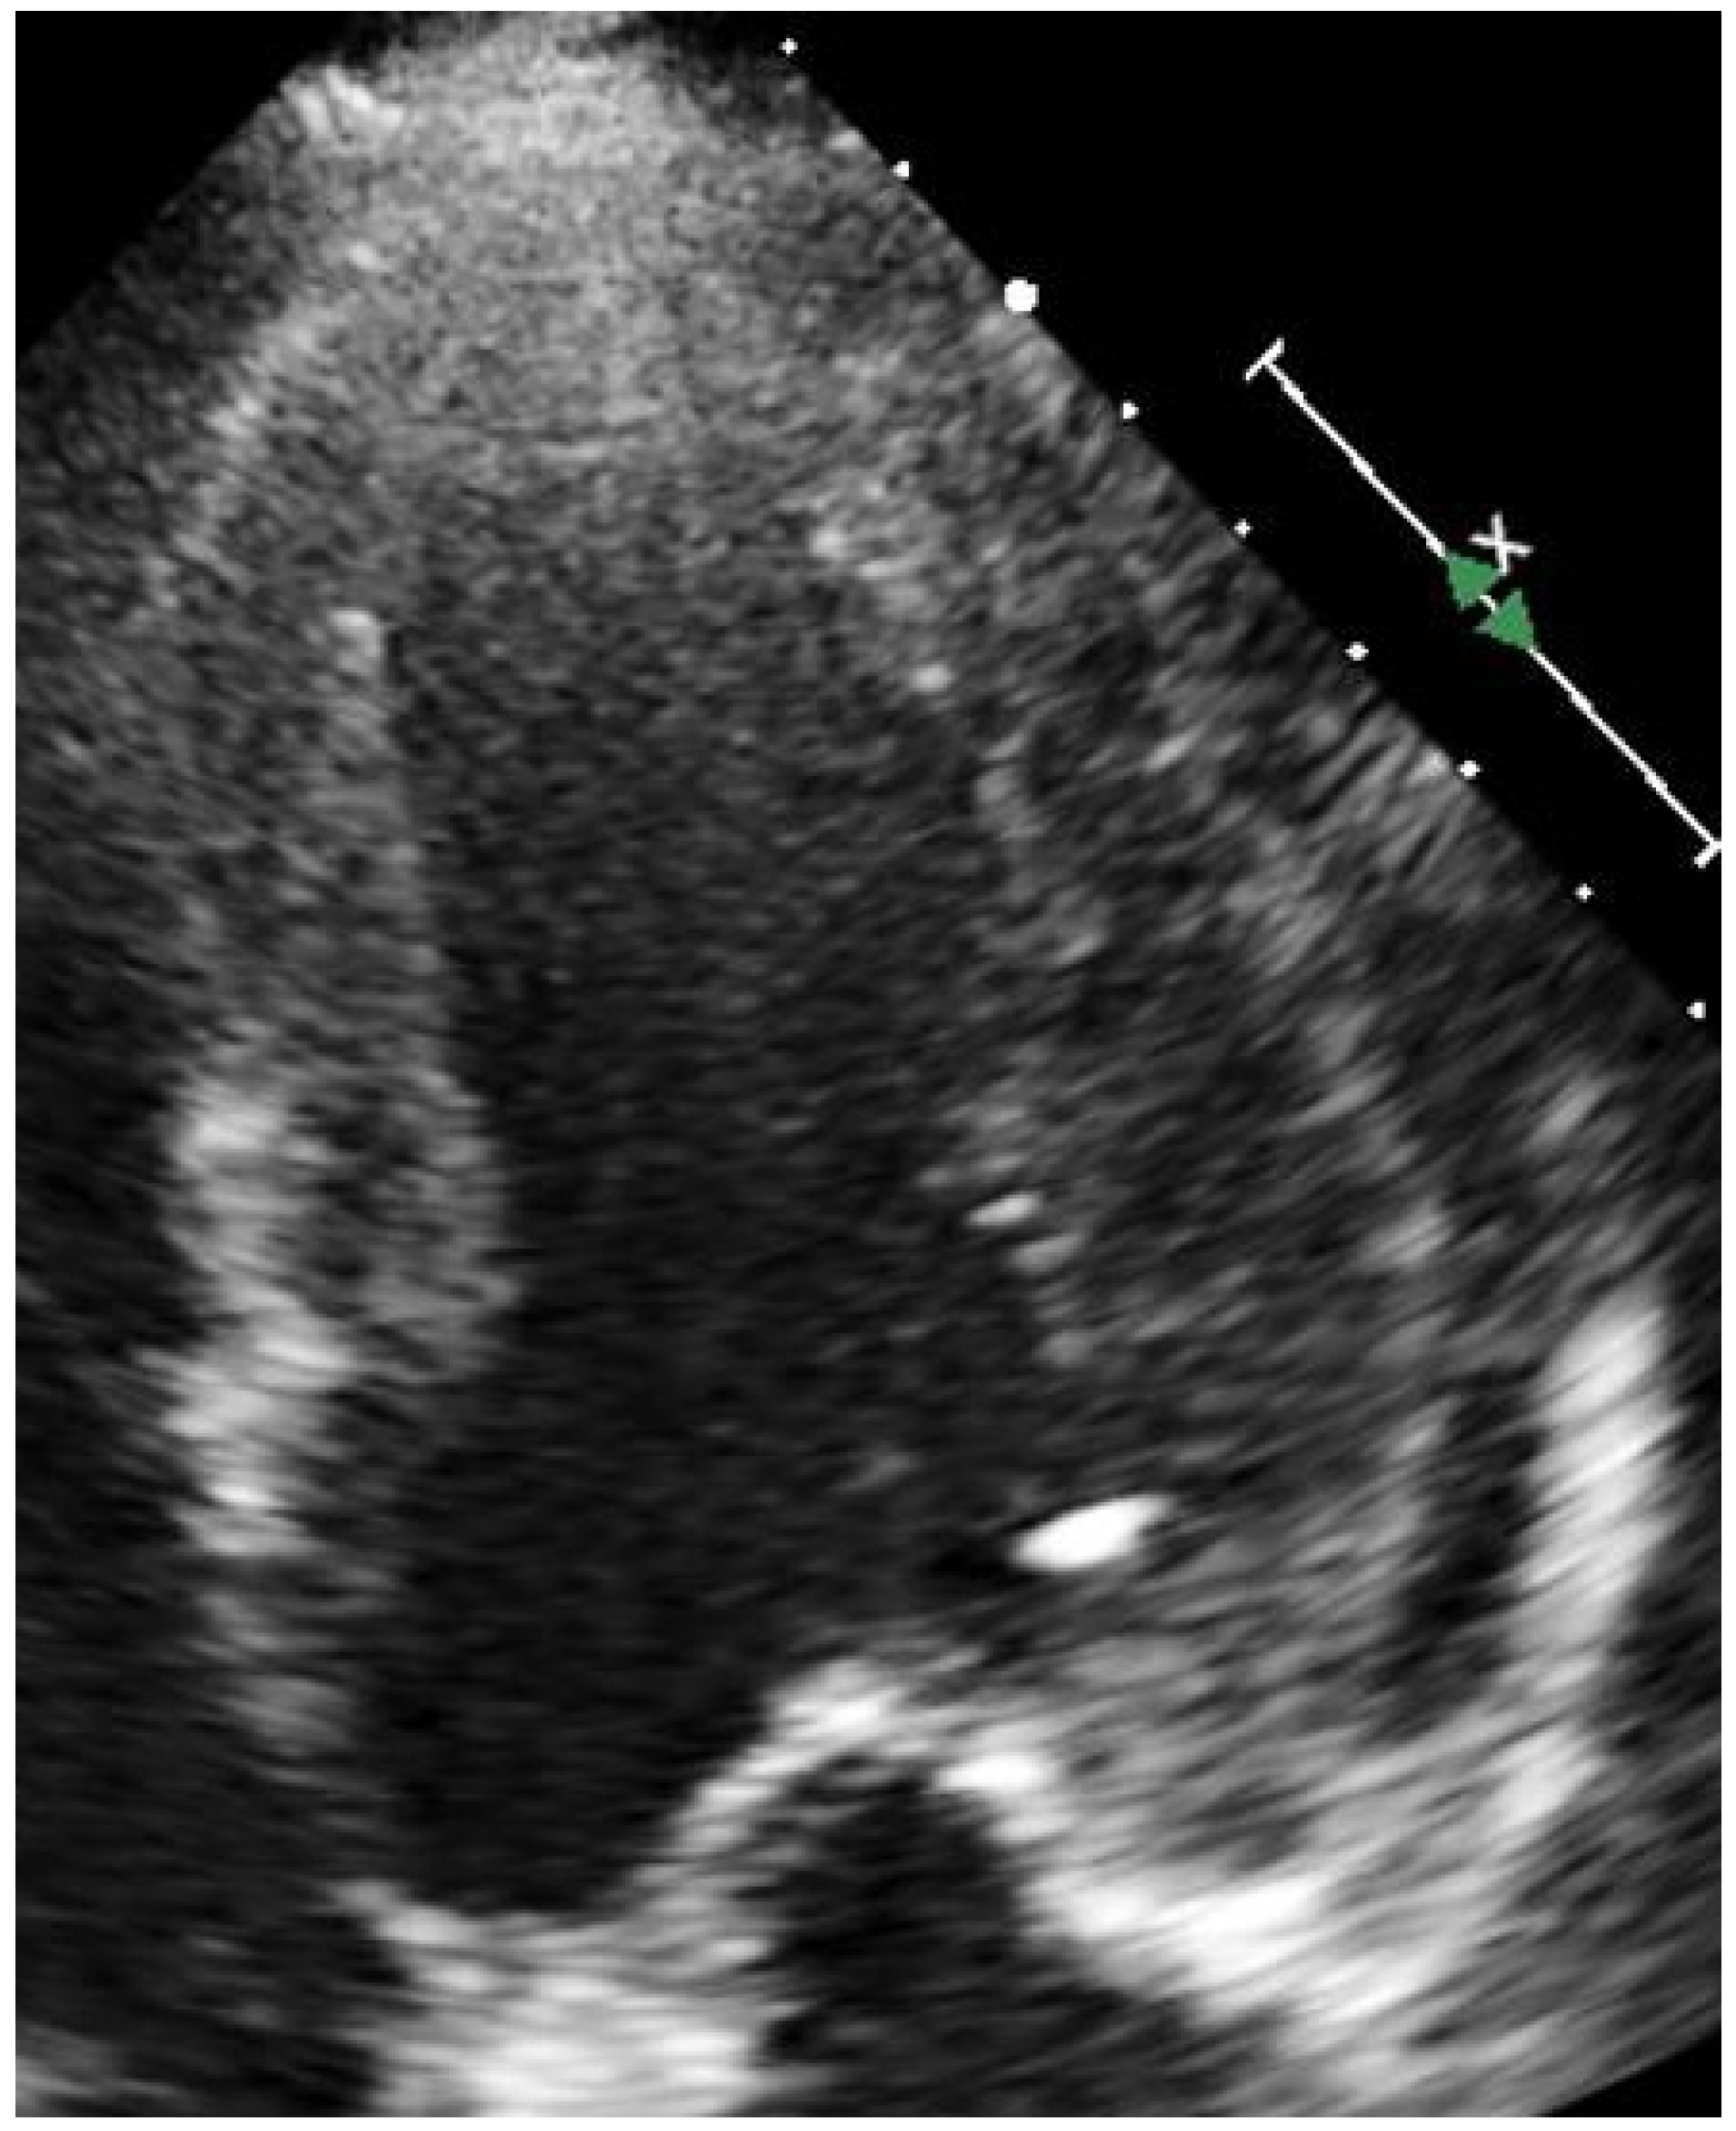

7. Non-Invasive Imaging: Ischaemia